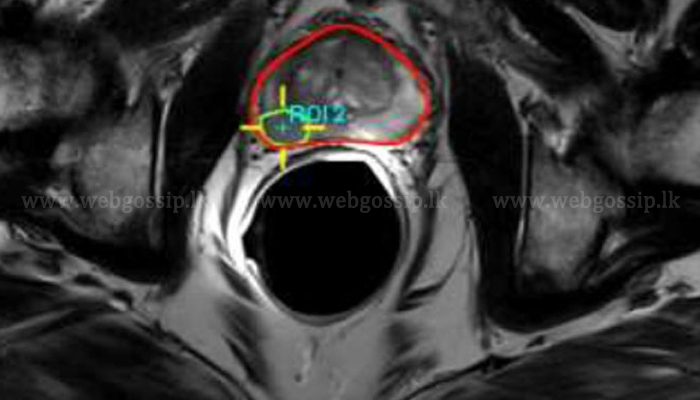

නෙදර්ලන්ත පර්‌යේෂණ ආයතනයක විද්‍යාඥයන් පිරිසක් විසින් අලුත් මිනිස් අවයවයක් සොයාගනු ලැබ තිබේ. එනම් උගුර ආශ්‍රිතව පිහිටා ඇති අලුත් ඛේට ග්‍රන්ථියකි. මෙතරම් කාලයකට පසු මේ ආකාරයෙන් අලුත් අවයවයක් සොයා ගැනීම බොහෝ දෙනෙකු තුළ විමතියක් ඇති කර තිබෙන ආකාරයක්ද දැකිය හැකි වේ. නෙදර්ලන්තයේ පිළිකා සම්බන්ධ ආයතනයක විද්‍යාඥයන් පිරිසක් තමුන්ගේ මෙම සොයා ගැනීම සම්බන්ධ විස්තර පසුගිය දා Radiotherapy and Oncology නමැති විද්‍යා සඟරාවක පළ කර තිබිණි. ඔවුන් මෙම අලුත් ග්‍රන්ථිය සොයාගෙන ඇත්තේ අහම්බෙන් බවක්ද සඳහන් වේ. මෙම අලුත් ග්‍රන්ථිය නම් කර ඇත්තේ ටියුබරියල් ඛේට ග්‍රන්ථිය නමිනි.

මෙය සාමාන්‍ය ස්කෑන් යන්ත්‍රවලට ද හසු නොවූ අවයවයක් බව සඳහන්ය. මෙතෙක් කලක් එය සොයා ගැනීමට නොහැකි වූයේ ද ඒ නිසා වීමට පිළිවන. කෙසේ නමුත් එය නිරීක්‍ෂණය කිරීමට හැකි වී ඇත්තේ PSMA PET (Prostate-Specific Membrane Antigen -Positron Emission Tomography) නමින් හැඳින්වෙන නව ස්කෑන් තාක්‍ෂණයක් හරහාය.